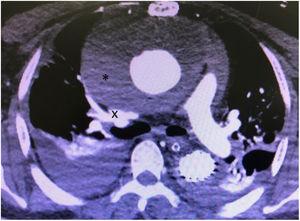

Manejo quirúrgico del carcinoma suprarrenal con trombo tumoral en la vena cava inferior

Beatriz Villota, Mikel Prieto, Arkaitz Perfecto, Andrés Valdivieso

Cir Esp. 2024;102:175

Acceso a texto completo